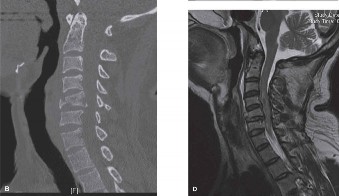

Treatment of an epidural abscess with neurological involvement? The most common organisms causing spinal epidural abscesses? CASE 5 A 62-year-old otherwise healthy woman presents to your clinic with complaints of both chronic low back pain and difficulty ambulating distances secondary to pain radiating into her buttocks and posterior thighs. She reports her pain is relieved with forward flexion. On examination, the patient has a forward flexed posture and 4/5 strength in her bilateral EHLs and left tibialis anterior muscle. She has failed nonoperative treatment including extensive physical therapy and epidural injections. Plain radiographs are shown in Figures 1–11 and 1–12. In addition, an MRI demonstrates significant central stenosis at L4–5 (not shown).

Figure 1–11

Figure 1–12

The best answer is (D). Both decompression (laminectomy) alone and a selective decompression and L4–5 (or L3–5) fusion have a high risk of worsening both the coronal and sagittal plane alignment. The long plate films demonstrate a typical de novo degenerative scoliosis with a coronal curve apex at L2–3, rotatory subluxation at L3–4, a fractional curve at L4–S1, and loss of lumbar lordosis. The most reliable method of treating this patient’s neurogenic claudication, sagittal imbalance, and listhesis is decompression and fusion with instrumentation from the thoracic spine to sacrum.

Optimal instrumentation construct for the surgical treatment of this condition? The most likely complications following surgery of this kind? CASE 6 You are evaluating a 15-year-old otherwise healthy boy in your clinic who has a primary complaint of low back pain. On examination, he has significant hamstring tightness but is otherwise neurologically normal. A lateral radiograph and sagittal T2 MRI are shown in Figures 1–13 and 1–14.

Figure 1–13

Figure 1–14

The correct answer is (C). The course of the L5 nerve root is subjected to compression within the neuroforamen in high-grade slips, and tension of the root over the ventral surface of the sacrum places it at the highest risk for dysfunction

following surgical reduction maneuvers.